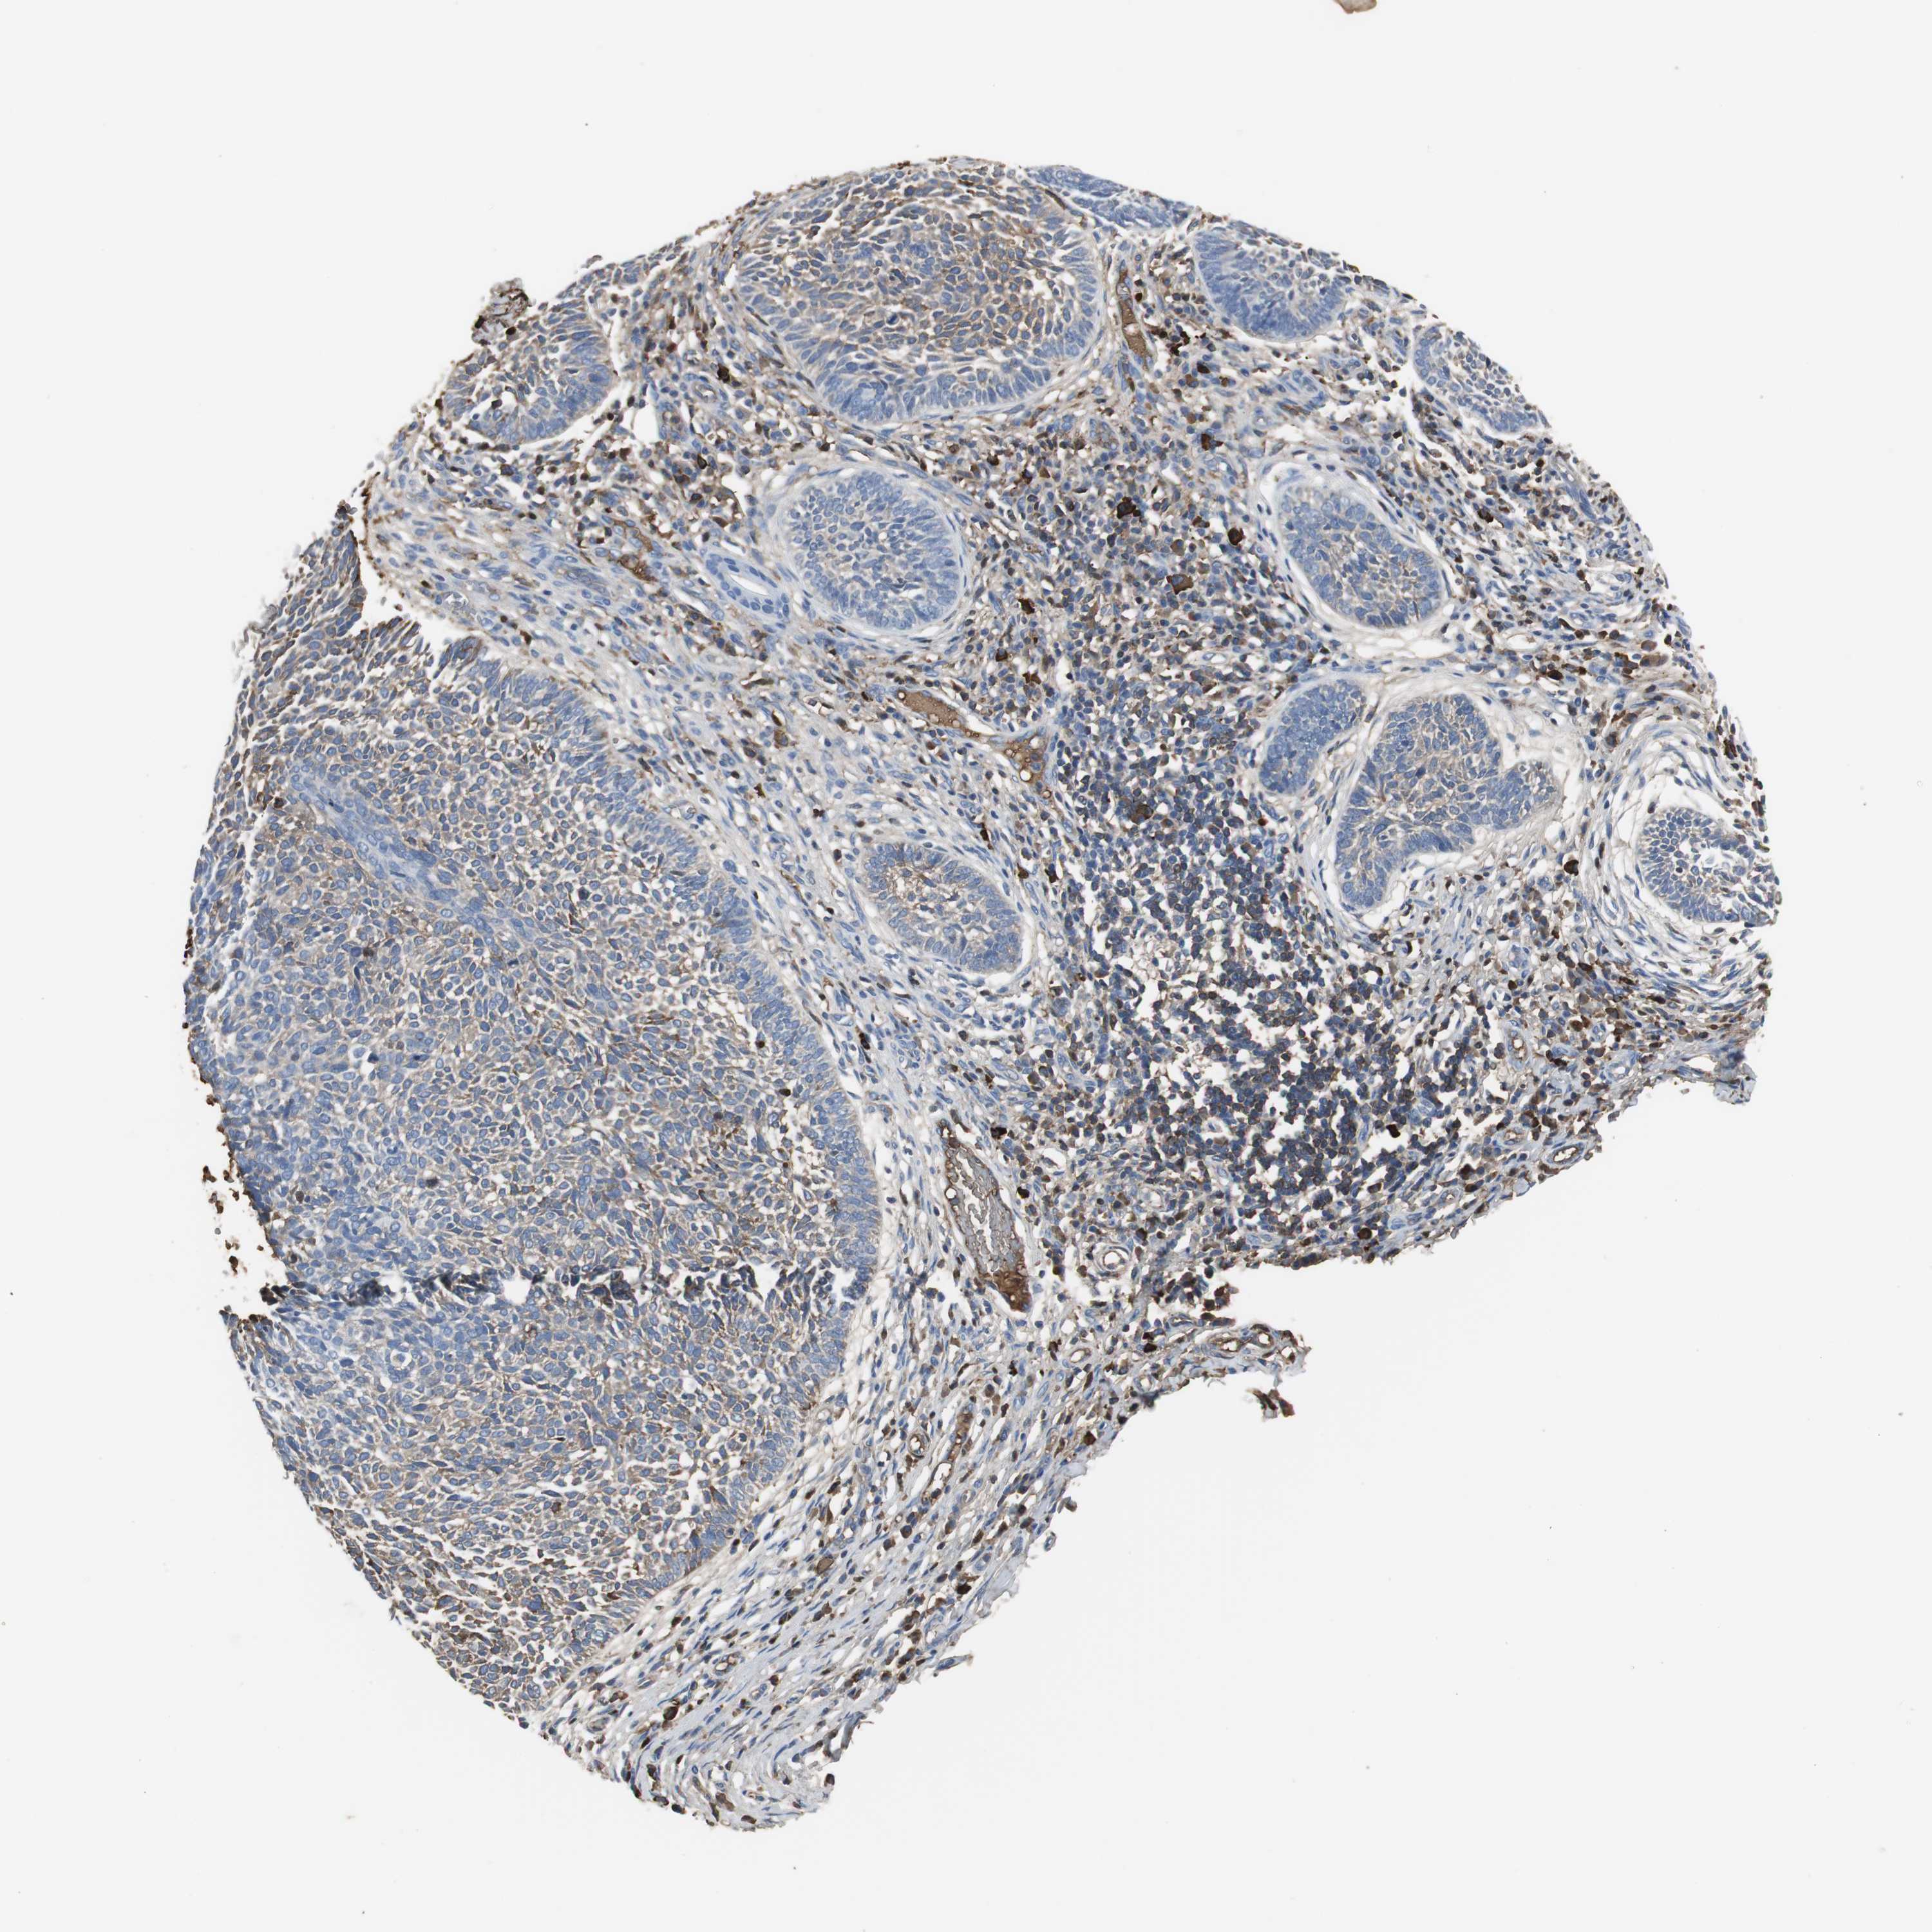

CANCER SKIN CANCER Show tissue menu

Basal cell and squamous cell cancer

SKIN CANCER - Protein expressioni

A mouse-over function shows sample information and annotation data. Click on an image to view it in a full screen mode. Samples can be filtered based on level of antibody staining by selecting one or several of the following categories: high, medium, low and not detected. The assay and annotation is described here.

Each image is clickable and will lead to virtual microscopy that enables deeper exploration of all samples and also displays staining intensity scores, fraction scores and subcellular localization as well as patient and tissue information for each sample.

Antibody HPA001217

Squamous cell carcinoma, NOS

Basal cell carcinoma